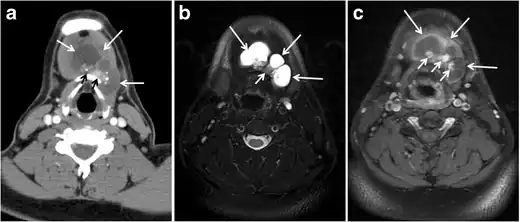

Fig. 6. A 61-year-old female patient with locally aggressive PTC. an Enhanced axial CT scan of the neck demonstrates a heterogeneous infiltrative thyroid mass. This mass diffusely involves the entire gland and circumferentially encases the trachea with involvement of bilateral tracheoesophageal grooves (white arrows). b, c Additional axial cranial images show right cricoid cartilage destruction (black arrows in b), right thyroid cartilage destruction (black arrow in c), right vocal cord paralysis (white arrows in b), and bilateral cervical lymphadenopathy (arrowheads).[1]

Fig. 11. Thyroid non-Hodgkin's large B-cell lymphoma in a 66-year-old female patient. an Axial enhanced neck CT scan demonstrates left thyroid lobe and isthmus homogeneously hypodense and minimally enhancing mass (white arrows). This lesion invades the prevertebral muscles (black arrows). Note the multiple enlarged level V lymph nodes (white arrowheads). b Post-treatment image shows significant reduction in size and mass effect of the left thyroid infiltrative mass, with almost complete resolution of the left cervical lymphadenopathy.[1]

Fig. 12. Diffuse thyroid large B-cell lymphoma in a 79-year-old female patient. an Axial enhanced neck CT scan demonstrates a homogeneously hypodense and minimally enhancing large right thyroid solid mass (long white arrow) extending into the thyroid isthmus. It is encasing the right carotid artery (short white arrow) and displacing of the trachea and oesophagus to the left side.[1]